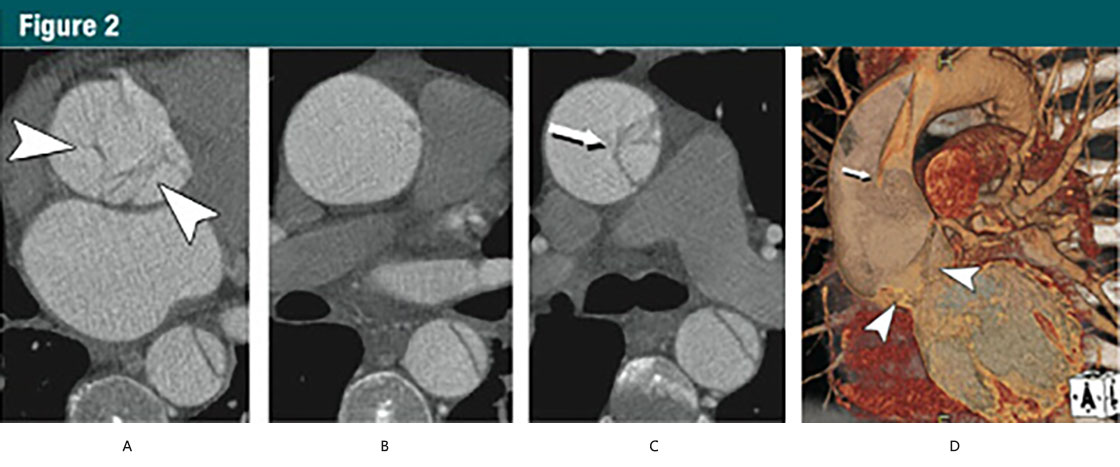

圖2 45歲,男,A型急性主動(dòng)脈夾層

(A-C)CT橫斷位圖像:

(A)主動(dòng)脈根部水平不規(guī)則線樣陰影(箭頭)

(B)升主動(dòng)脈中段沒有夾層皮瓣

(C)升主動(dòng)脈遠(yuǎn)端可見夾在真、假腔之間的夾層皮瓣(細(xì)箭)

(D)VR重建展示夾層,近端夾層撕裂皮瓣下垂向下通過主動(dòng)脈瓣膜(箭頭)。細(xì)箭所指遠(yuǎn)端升主動(dòng)脈的夾層皮瓣。在無ECG門控的時(shí)候,這些細(xì)微的發(fā)現(xiàn)并不可見。(轉(zhuǎn)載、許可、引用30)

由于有著共同的病理改變,代表主動(dòng)脈夾層及其變異的第一組病變都是動(dòng)脈壁中層病變。典型夾層的征象是主動(dòng)脈壁內(nèi)形成一個(gè)通道或者假腔,后者通過撕裂的內(nèi)膜與真腔分離(圖2)。

Group 1 lesions representing aortic dissection and its variants share a diseased aorticmedia as their common pathologic lesion. Classic dissection is characterized by the development of a flow channel or false lumen within the aortic wall, which is separated from the true lumen by a dissection membrane (Fig2).